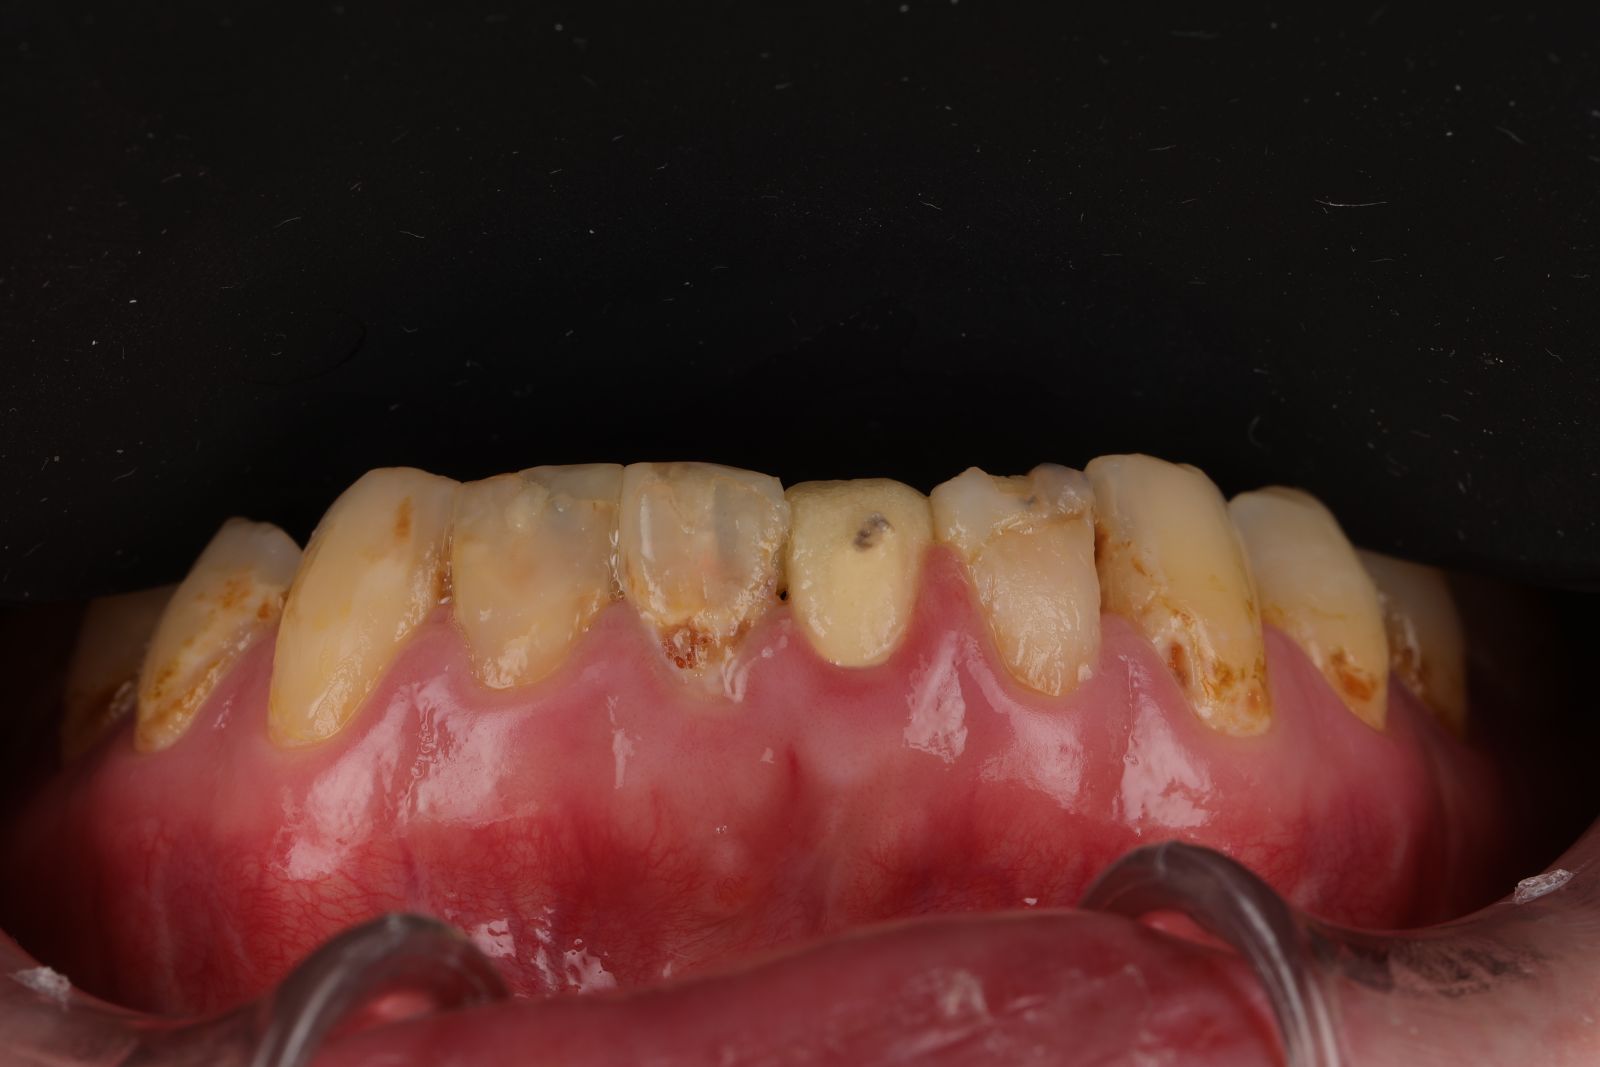

【 案 例 二】

-

患者因為以前做的金屬假牙邊緣不密合,被金屬染色變黑,以及抽過神經犬齒變色影響美觀。

希望牙齒前牙區能一致變白,型態上也希望能調整得更自然,跟醫生討論之下決定把笑容區6顆牙齒都一起做前牙美學,用全瓷冠搭配美白貼片一起處理!

- 先把舊的假牙拆除後換成臨時假牙,期間先做冷光美白讓牙齒的基礎顏色變白,用保養型冷光美白,讓其他自然牙的部分可以白2~3個色階。一段時間讓顏色穩定後就可以當作正式全瓷冠的顏色參考。